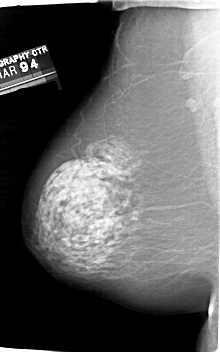

A_1829_1.LEFT_CC

LEFT_CC LINES 6751 PIXELS_PER_LINE 4006 BITS_PER_PIXEL 12 RESOLUTION 43.5 NON_OVERLAY